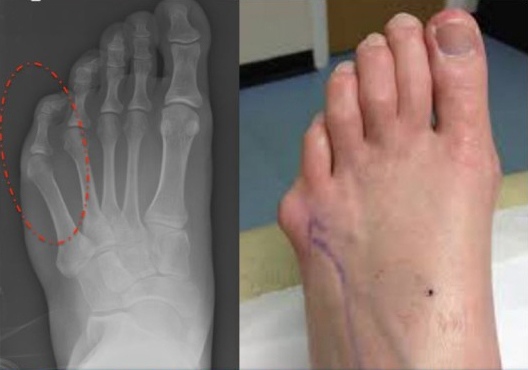

2일 의료계에 따르면 소건막류는 새끼발가락이 바깥으로 돌출되면서 발생하는 족부질환이다. 이는 엄지발가락이 바깥으로 돌출되면서 발생하는 질환인 ‘무지외반증’의 반대라고 생각하면 쉽다.

소건막류는 대부분 후천적으로 발생한다. 새끼발가락이 돌출되기 때문에 증세가 심해지면 바로 알 수 있지만 눈으로 확인하기 전에도 신호가 온다. 유난히 새끼발가락이 아프고 빨갛게 변하거나 발바닥에 굳은살이 생긴다면 소건막류를 의심해 볼 수 있다.